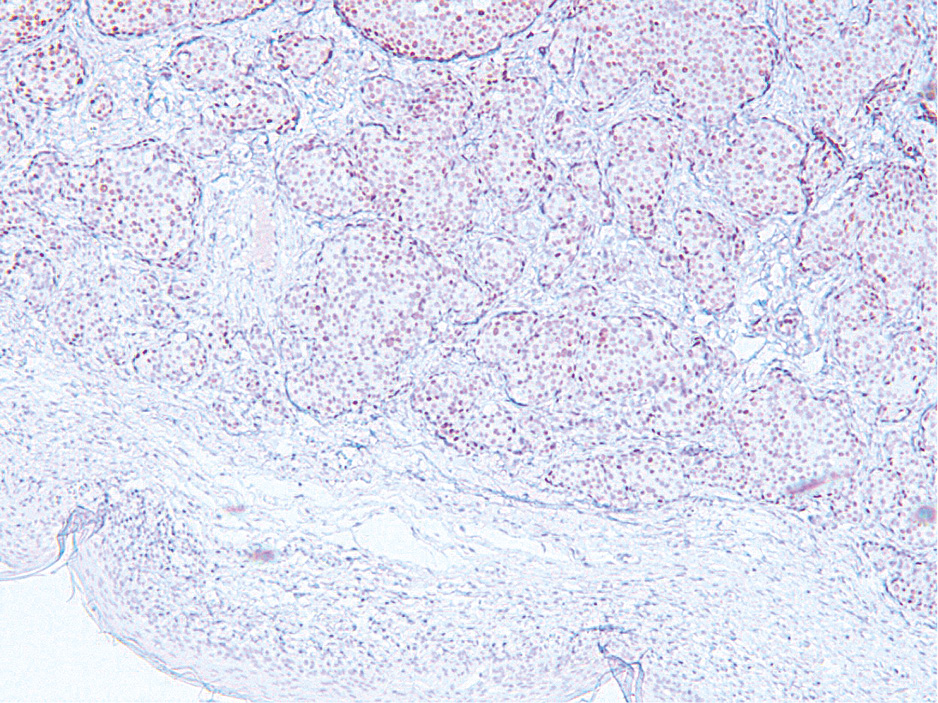

Рис. 4. Иммуногистохимическое исследование операционного материала. Диффузная слабая ядерная экспрессия рецепторов прогестерона в клетках опухоли, ×10.

Fig. 4. Immunohistochemical examination of the surgical specimen. Diffuse weak nuclear expression of progesterone receptors in tumor cells, ×10.

При иммуногистохимическом исследовании клетки опухоли сильно и диффузно экспрессируют рецепторы эстрогенов – ER (рис. 3), слабо и диффузно рецепторы прогестерона (рис. 4), а также сильно и очагово-диффузно раково-эмбриональный антиген – СЕА (рис. 5) и антиген эпителиальных мембран (ЕМА). Индекс пролиферативной активности Ki67 менее 20% (рис. 6), а рецептор эпидермального фактора роста человека 2-го типа Her2 – отрицательный. Опухоль не экспрессирует цитокератины СК 5/6, Р63 и маммаглобин.